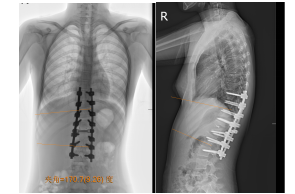

患者15岁,正是花季的年龄,其腰渐渐地疼痛和变形,到医院就诊,诊断为先天性半椎体畸形,让她陷入了恐慌和绝望中。

▲ 术前Cobb 角侧凸57°后凸82°

正当以为她的青春与学业无法为继的时候,脊柱外科米明珊专家团队让她重新燃起了希望之光。

在完善检查准备工作后,对她实施了后路一期半椎切除侧后凸畸形矫形重建手术。切除半椎体后,为了减轻脊髓的张力减少皱褶产生的后遗症。创新性地应用了椎间融合器来平衡缺损区加速病变节段的融合防止畸形复发。

▲ 术后Cobb角侧凸9°后凸10°,矫正满意

术后畸形消失,在加速康复小组治疗后,患者仅用3周就恢复了正常行走,如期佩戴支具,回到了校园继续努力学习生活。